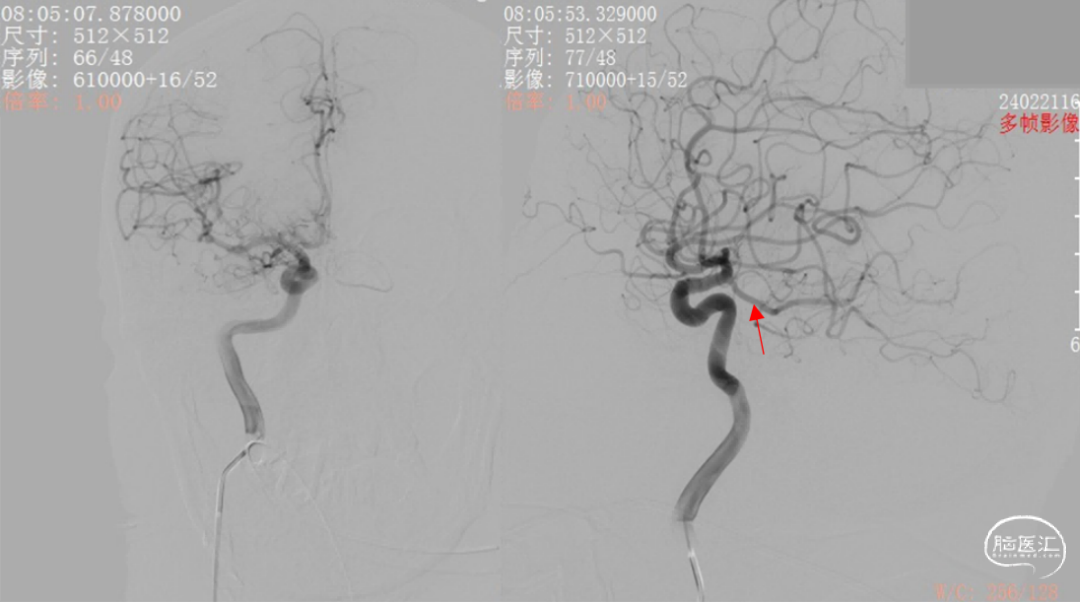

图4. 右侧颈内动脉造影提示胚胎型后交通动脉

综合术前辅助检查,(Core+pen)/Core=3.58;Pen>15ml;Core<70ml(图3);发病时间小于24小时,存在取栓指征,但是当地医院手术经验告诉我们左侧椎动脉慢性闭塞,且开通异常困难,常规手术方案很难成行,术前制定合理且可行的手术方案至关重要。方案1:仍采用左侧椎动脉+基底动脉取栓的正向开通方案,可能会继续浪费大量时间,甚至最后以失败告终。方案2:采用右侧椎动脉入路,由于右侧椎动脉V4段发育不良,当地医院已尝试过超选,证实无法通过V4段至基底动脉建立取栓通路。方案3:既往有文献报道开颅椎动脉直视下穿刺取栓,虽然方案可行,但我院无类似手术经验,贸然尝试风险难以把控。方案4:回顾当地医院取栓影像资料,发现双侧颈内动脉后交通呈胚胎型,是否可能通过后交通跨循环逆向超选至基底动脉取栓。患者平卧DSA床,全麻插管成功后,用碘伏常规消毒手术区皮肤,铺无菌巾单。取双侧股动脉为穿刺点,于14时00分seldinger法穿刺成功后分别置入8F穿刺鞘和5F 短鞘。行全脑血管造影显示左侧椎动脉起始部闭塞,颈升动脉通过肌支代偿V2及以远的椎动脉血流,右侧椎动脉V4段发育不良,单纯供应右侧PICA,双侧后交通动脉胚胎型。(图9,图10)首先我们仍尝试传统入路进行超选左侧椎动脉,发现左侧椎动脉开口闭塞,斑块质地坚硬,微导丝微导管无法通过。短暂尝试无果后,迅速改为右侧椎动脉入路,发现将微导丝塑型成“J”型或成袢,均无法到达右侧椎动脉V4段,遂果断决定采用跨循环取栓方案。将5F VERT造影导管超选至左侧锁骨下动脉,进行正向血流监测。6F 90cm长鞘(cook)及5F 125cm Navien导管在泥鳅导丝带领下超选进入右侧颈内动脉岩骨段。随后将Rebar18微导管在Synchro2微导丝带领下超选至大脑中动脉,并将Navien带领至右侧颈内动脉交通段。微导丝微导管回撤至颈内动脉,路图下Synchro2微导丝带领Rebar18逐步通过右侧后交通动脉,再在透视下经右侧大脑后动脉P1段盲超选至基底动脉下段。(图11-13)手推造影确认Rebar18微导管已突破血栓段,并在基底动脉真腔内。(图14)经Rebar18释放一枚solitaire FR支架(4mm×20mm)覆盖血栓段。SWIM技术负压下抽拉支架1次,抽拉过程中时刻注意系统张力,逐步回撤支架同时适度回撤Navien释放张力,以保证Navien贴近后交通开口而不向后交通动脉内继续深入。撤出支架后,Navien原位保持负压约30秒。(图15)造影复查见基底动脉及其分支再通,支架取出少量血栓(图18)。于14时45分达到远端血流mTICI3级,10分钟后复查造影显示血管通畅,于14时55分末次造影见远端血流维持mTICI3级。(图16,17)术中Dynamic CT未见明显术区出血(图19)。遂缝合穿刺点,结束手术。手术顺利,术中病人情况稳定。术末血压115/58mmHg,脉搏70次/分,呼吸12次/分,氧饱和度100%。术毕送重症监护室。图9. 双侧椎动脉造影:左侧椎动脉起始部闭塞,左侧颈升动脉肌支和右侧椎动脉通过脊髓支代偿V2及以远的椎动脉血流;右侧椎动脉V4段发育不良,单纯供应右侧PICA

图10. 右侧颈总动脉造影:后交通动脉胚胎型